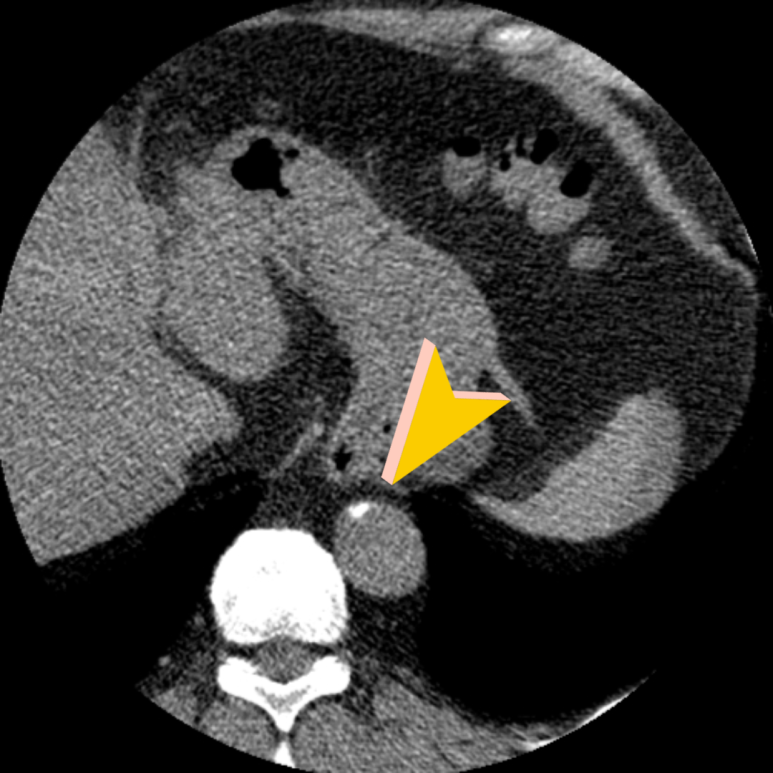

• 상행 대동맥 석회화 상행 대동맥 석회화

• 하행 대동맥 석회화 하행 대동맥 석회화